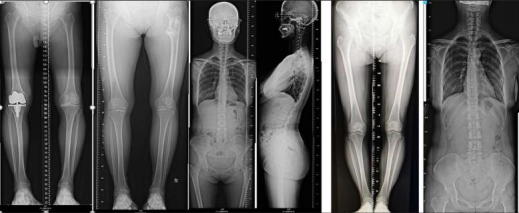

长骨拼接功能

该设备的长骨拼接功能,可根据需要连续拍摄3-4张图像,并将 图像按真实解构结构拼接成一张整图。